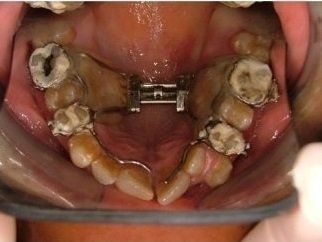

Il trattamento ortodontico non è solo per i bambini: se hai denti storti, affollati, mancanti o prominenti che ti impediscono di masticare e parlare liberamente, potrebbe essere necessario rivolgersi a uno specialista. L’ortodonzia prevede l'uso di apparecchi ortodontici, che possono essere fissi o rimovibili.

I dentisti studiano infatti le anomalie di costituzione, posizione e sviluppo di denti e ossa mascellari, e progettano l’apparecchio mirando al ripristino della corretta funzionalità dell'apparato masticatorio.